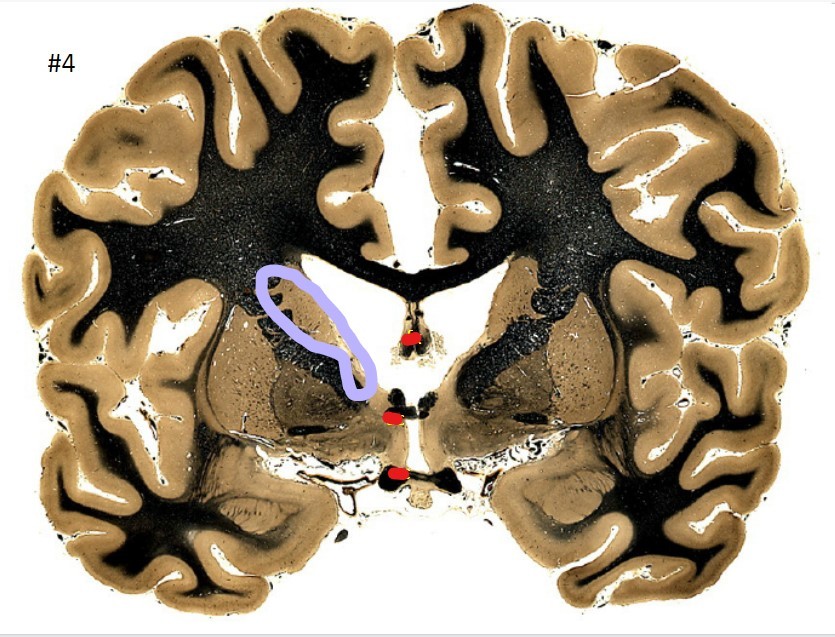

10

Q

what is the circled area (#4)?

A

the fornix

How well did you know this?

11

the anterior commissure

12

the optic chiasm

13

the putamen

14

the globus pallidus

15

the internal capsule

16

the caudate nucleus

17

the corpus striatum

18

19